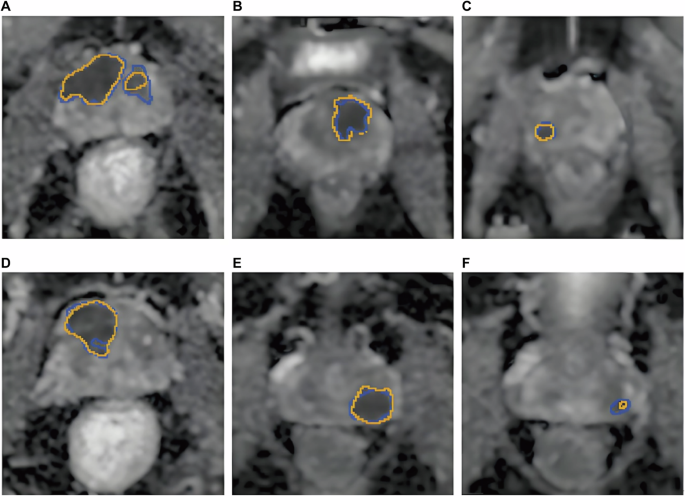

In terms of end-to-end models, Liu et al. proposed a Transformer-based multi-sequence fusion model (ViT-MRI). The T2WI, DWI, and DCE-MRI sequences were input into the Vision Transformer (ViT) encoder, respectively, and a cross-attention mechanism was used for multi-modal feature fusion, and a probability map of csPCa was output25. A total of 1500 patients were included in this study. The results showed that the AUROC of this model for identifying csPCa in the test set was 0.94, with a sensitivity of 91.2% and a specificity of 88.5%, which was significantly better than that of 3 senior radiologists (AUROC: 0.85-0.88). Further research found that the detection rate of the model for small csPCa ≤1 cm was as high as 87.3%, while the average detection rate of physicians was 72.1%, indicating that AI is superior to humans in detecting small lesions, as shown in Fig. 3.

The figure shows the performance of the ViT-MRI model compared with three senior radiologists in detecting clinically significant prostate cancer (csPCa)37. Panels A–F display example prediction results and corresponding ADC maps. The yellow lines indicate the AI-predicted lesion boundaries, which are highly consistent with the manual annotations (A–F) performed by experienced genitourinary radiologists based on pathological results.